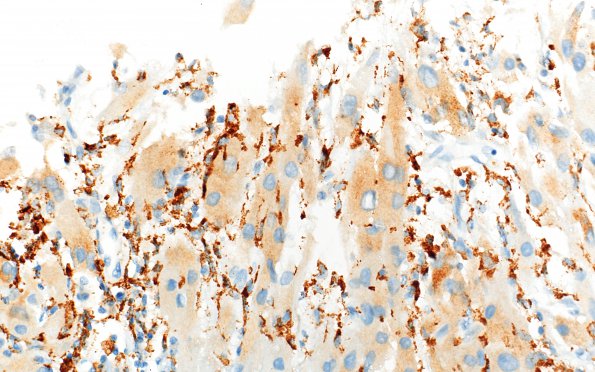

1C5 Granular Cell Tumor (Case 1) CD68 40X 2A

Patches of more strongly stained elements (CD68 IHC)